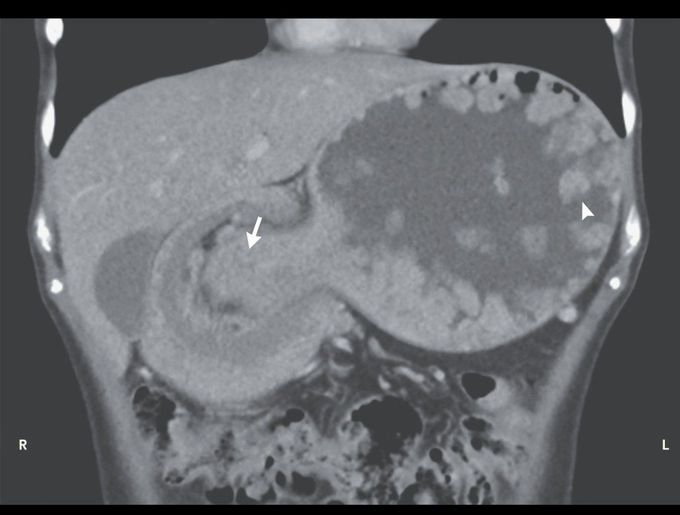

A 26-year-old woman with a known history of the Peutz–Jeghers syndrome presented to the emergency department with a 1-week history of abdominal pain and nonbilious vomiting. The heart rate was 110 beats per minute, and the blood pressure 120/90 mm Hg. On examination, a tender mass was palpable in the upper abdomen. Computed tomography of the abdomen revealed multiple gastric polyps (arrowhead) and gastrogastric intussusception extending into the duodenum (arrow). Gastrogastric intussusception is an uncommon but serious complication of the Peutz–Jeghers syndrome. The patient underwent an emergency laparotomy, which revealed a large, palpable, polypoid mass in the distal stomach. The intussusceptum was found to be necrotic, and a distal gastrectomy was performed. A Billroth I gastroduodenostomy was constructed to preserve bowel length and to allow for future endoscopic access. The patient recovered well after surgery and was discharged 7 days after presentation. She reported feeling well at follow-up 6 weeks later.